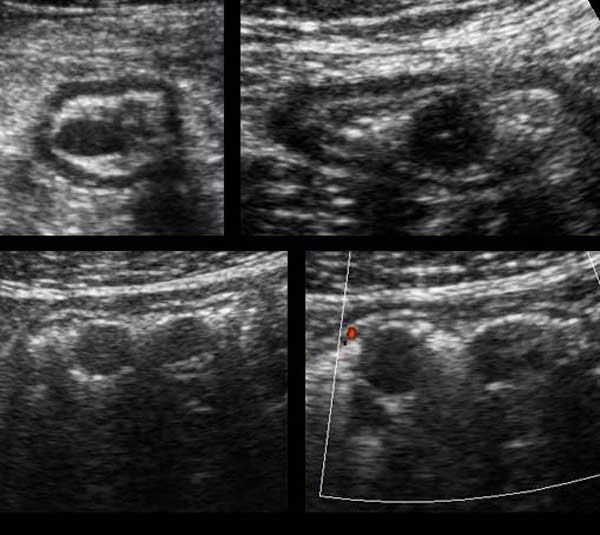

Gynecology pelvic ultrasound made easy step by step guide Artofit